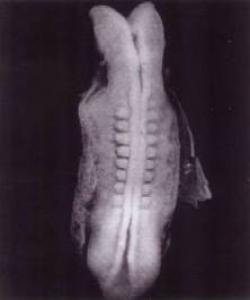

كاتێك نوتفەی پیاو لەگەڵ هێلكۆكەی ئافرەت یەكدەگرێت ئەوا جەوهەری كۆرپەلە چاوەڕوانكراوەكە پێكدێت، ئەو تاكە خانەیەی كە ناودەبرێت بە زایگۆت (لاقحە – Zygote - هێلكەی پیتراو) دەستبەجێ دەست بە زۆربوون دەكات بەڕێگای دابەشبوون. لە كۆتاییدا دەبێتە پارچەیەك گۆشت كە پێیدەوترێت كۆرپەلە (embry)، ئەمەش بەهۆی مایكرۆسكۆبەوە نەبێت نابینرێت.

كۆرپەلە ماوەی گەشەكردنی لە بۆشاییدا بەسەر نابات، بەڵكو بە منداڵدانەوە پەیوەست دەبێت، بەتەواوی وەك پەیوەستی و جێگیربوونی ڕەگەكان لە خاكدا بەهۆی (تەرز)ەكانیانەوە. لە ڕێی ئەم پێكەوە بەسترانەوە كۆرپەلە دەتوانێت ماددە پێویستیەكان بۆ گەشەكردنی خۆی لە لەشی دایكیەوە وەربگرێت.

ئەم خاڵە بۆخۆی موعجیزەیەكی قورئان ئاشكرا دەكات، بۆ وەسفی گەشەكردنی كۆرپەلە لە منداڵدانی دایكدا وشەی (علق) بەكاردەهێنێت، وەك دەفەرموێت:

{اقْرَأْ بِاسْمِ رَبِّكَ الَّذِي خَلَقَ (1) خَلَقَ الْإِنْسَانَ مِنْ عَلَقٍ (2) اقْرَأْ وَرَبُّكَ الْأَكْرَمُ (3)} [العلق] واتە: (ئەی محمد (صلى الله عليه وسلم)) بخوێنە بەناوی ئەو پەروەردگارەتەوە كە هەموو شتێكی درووستكردووە، ئادەمیزادی لە چەند خانەیەكی خۆهەڵواسەر (لەناو منداڵداندا) دروستكردووە، بخوێنە، پەروەردگاری تۆ خاوەنی ڕێز و بەخششی بێسنوورە.

(علق) لە زمانەوانیدا ئەو شتەیە كە بەشوێنێكەوە دەلكێت. هەروەها وشەكەش خۆی بۆ (زەرو – علق) بەكاردەهێنرێت كە بەلەشەوە دەلكێت وخوێن دەمژێت.

بێگومان بەكارهێنانی ئەو وشە گونجاوە بۆ وەسفی گەشەكردنی كۆرپەلە لە منداڵدانی دایكدا، جارێكی تر ئەوە دەسەلمێنێت كە قورئان نیگایە لەخوای گەورەوەیە و گوتراوی ئەو زاتەیە.